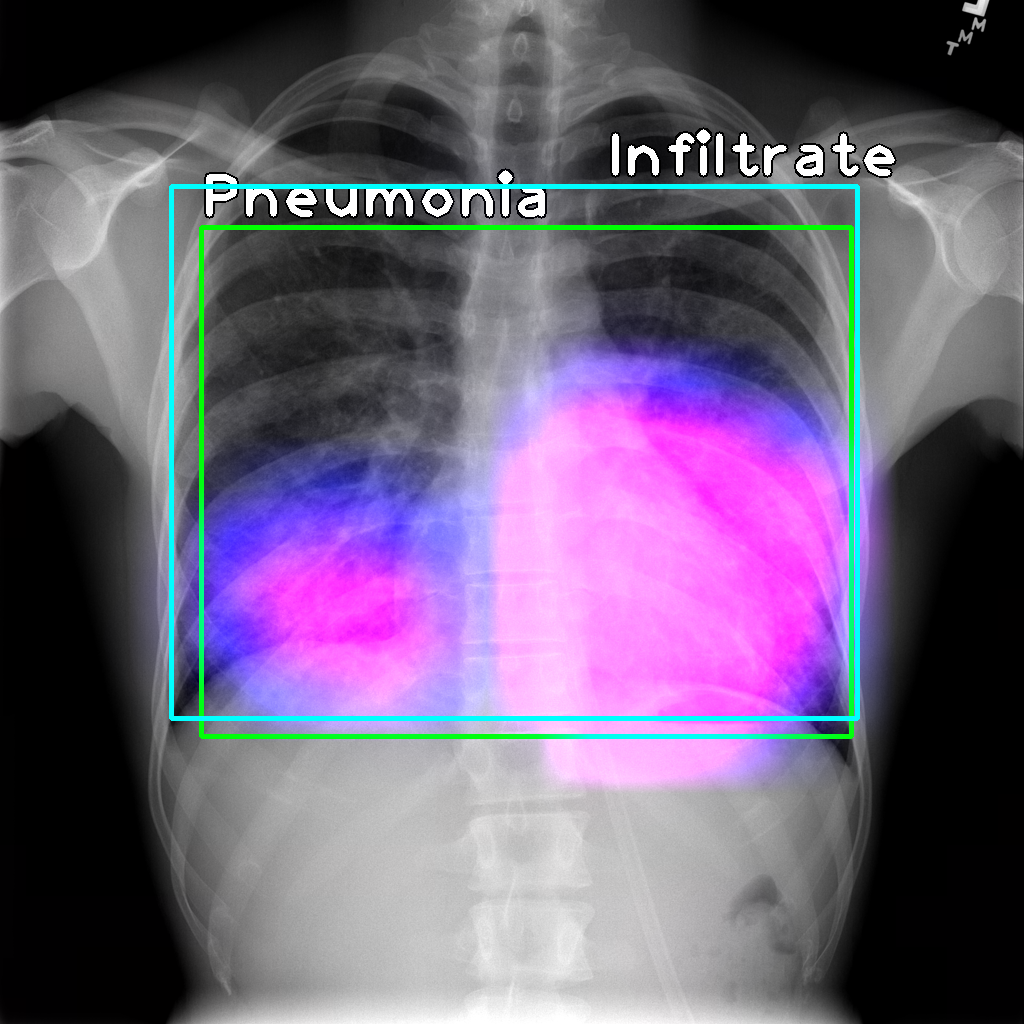

We note that the IoR data is fairly similar to the IoU data, and most of the observations above hold in this case as well. Qualitative examples of the localizations derived are shown in Figure 1.